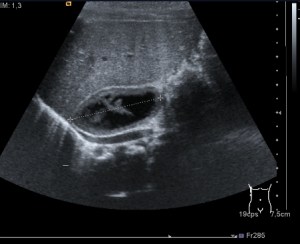

- Vesícula biliar: Visualizada como una estructura en forma de pera, que puede variar en tamaño según la cantidad de bilis que contenga. Su pared aparece como una línea hiperecogénica y suele tener un grosor menor a 3 mm.

- Lumen: Es la cavidad interna de la vesícula biliar donde se almacena la bilis. Se visualiza como una zona anecoica (sin ecos) rodeada por la pared hiperecogénica.

- Colelitiasis: La colelitiasis se refiere a la formación de cálculos biliares en la vesícula biliar. Estos cálculos se pueden identificar en la ecografía como estructuras hiperecogénicas dentro de la vesícula. Pueden variar en tamaño y cantidad. Las colelitiasis deben ser estructuras móviles con sombra acústica posterior e hiperecogénicas.